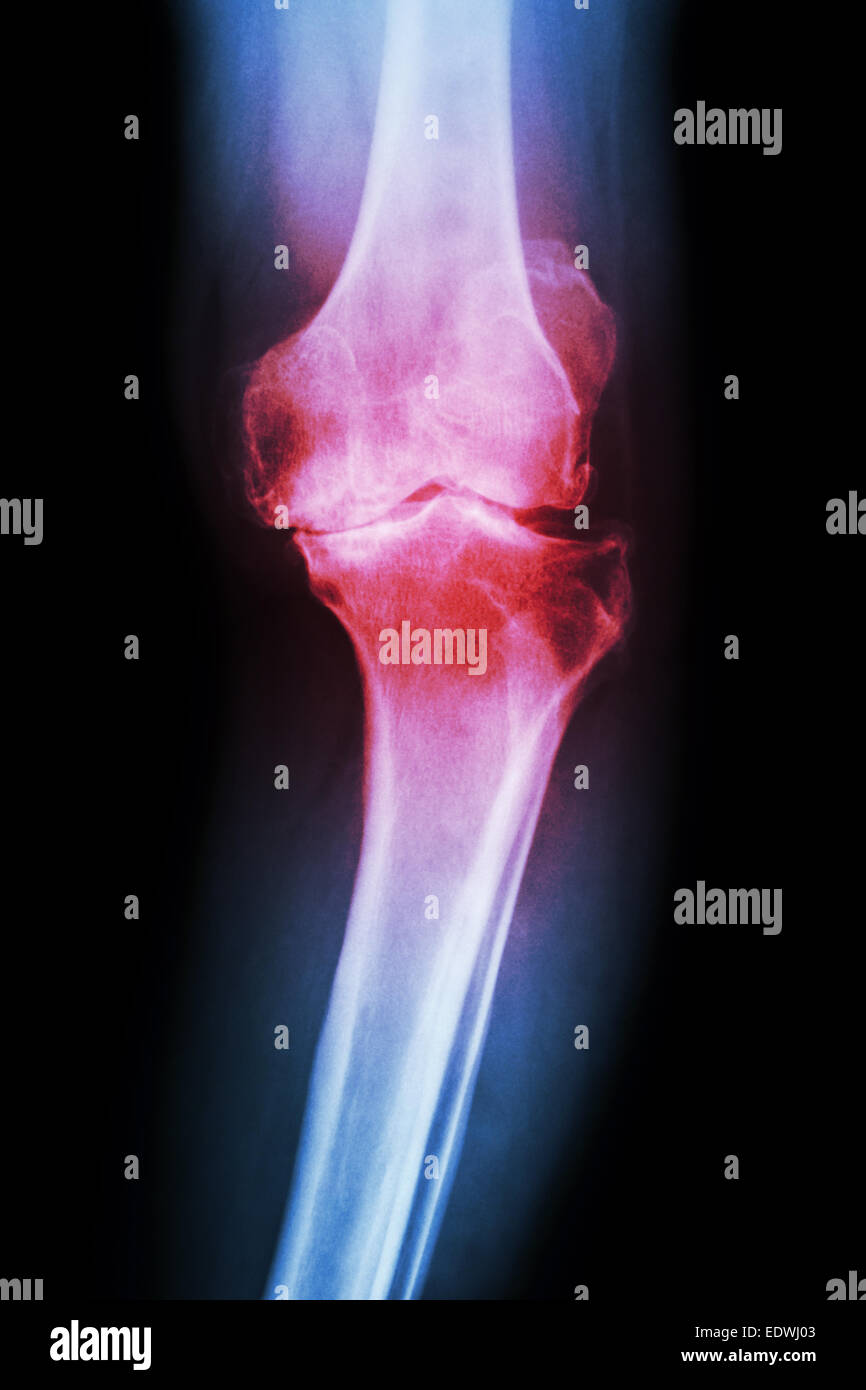

Film x-ray articulation du genou avec l'arthrite ( la goutte, l'arthrite rhumatoïde, l'arthrite septique , l'arthrose du genou ) et la zone vide sous Banque D'Imageshttps://www.alamyimages.fr/image-license-details/?v=1https://www.alamyimages.fr/photo-image-film-x-ray-articulation-du-genou-avec-l-arthrite-la-goutte-l-arthrite-rhumatoide-l-arthrite-septique-l-arthrose-du-genou-et-la-zone-vide-sous-88388299.html

Film x-ray articulation du genou avec l'arthrite ( la goutte, l'arthrite rhumatoïde, l'arthrite septique , l'arthrose du genou ) et la zone vide sous Banque D'Imageshttps://www.alamyimages.fr/image-license-details/?v=1https://www.alamyimages.fr/photo-image-film-x-ray-articulation-du-genou-avec-l-arthrite-la-goutte-l-arthrite-rhumatoide-l-arthrite-septique-l-arthrose-du-genou-et-la-zone-vide-sous-88388299.htmlRFF3PC4Y–Film x-ray articulation du genou avec l'arthrite ( la goutte, l'arthrite rhumatoïde, l'arthrite septique , l'arthrose du genou ) et la zone vide sous

Film x-ray articulation du genou avec l'arthrite ( la goutte, l'arthrite rhumatoïde, l'arthrite septique , l'arthrose du genou ) et la zone vide sous Banque D'Imageshttps://www.alamyimages.fr/image-license-details/?v=1https://www.alamyimages.fr/photo-image-film-x-ray-articulation-du-genou-avec-l-arthrite-la-goutte-l-arthrite-rhumatoide-l-arthrite-septique-l-arthrose-du-genou-et-la-zone-vide-sous-88388298.html

Film x-ray articulation du genou avec l'arthrite ( la goutte, l'arthrite rhumatoïde, l'arthrite septique , l'arthrose du genou ) et la zone vide sous Banque D'Imageshttps://www.alamyimages.fr/image-license-details/?v=1https://www.alamyimages.fr/photo-image-film-x-ray-articulation-du-genou-avec-l-arthrite-la-goutte-l-arthrite-rhumatoide-l-arthrite-septique-l-arthrose-du-genou-et-la-zone-vide-sous-88388298.htmlRFF3PC4X–Film x-ray articulation du genou avec l'arthrite ( la goutte, l'arthrite rhumatoïde, l'arthrite septique , l'arthrose du genou ) et la zone vide sous

Film x-ray articulation du genou avec l'arthrite ( la goutte, l'arthrite rhumatoïde, l'arthrite septique , l'arthrose du genou ) et la zone vide sous Banque D'Imageshttps://www.alamyimages.fr/image-license-details/?v=1https://www.alamyimages.fr/photo-image-film-x-ray-articulation-du-genou-avec-l-arthrite-la-goutte-l-arthrite-rhumatoide-l-arthrite-septique-l-arthrose-du-genou-et-la-zone-vide-sous-88388301.html

Film x-ray articulation du genou avec l'arthrite ( la goutte, l'arthrite rhumatoïde, l'arthrite septique , l'arthrose du genou ) et la zone vide sous Banque D'Imageshttps://www.alamyimages.fr/image-license-details/?v=1https://www.alamyimages.fr/photo-image-film-x-ray-articulation-du-genou-avec-l-arthrite-la-goutte-l-arthrite-rhumatoide-l-arthrite-septique-l-arthrose-du-genou-et-la-zone-vide-sous-88388301.htmlRFF3PC51–Film x-ray articulation du genou avec l'arthrite ( la goutte, l'arthrite rhumatoïde, l'arthrite septique , l'arthrose du genou ) et la zone vide sous

Film x-ray articulation du genou avec l'arthrite ( la goutte, l'arthrite rhumatoïde, l'arthrite septique , l'arthrose du genou ) et la zone vide sous Banque D'Imageshttps://www.alamyimages.fr/image-license-details/?v=1https://www.alamyimages.fr/photo-image-film-x-ray-articulation-du-genou-avec-l-arthrite-la-goutte-l-arthrite-rhumatoide-l-arthrite-septique-l-arthrose-du-genou-et-la-zone-vide-sous-88388300.html

Film x-ray articulation du genou avec l'arthrite ( la goutte, l'arthrite rhumatoïde, l'arthrite septique , l'arthrose du genou ) et la zone vide sous Banque D'Imageshttps://www.alamyimages.fr/image-license-details/?v=1https://www.alamyimages.fr/photo-image-film-x-ray-articulation-du-genou-avec-l-arthrite-la-goutte-l-arthrite-rhumatoide-l-arthrite-septique-l-arthrose-du-genou-et-la-zone-vide-sous-88388300.htmlRFF3PC50–Film x-ray articulation du genou avec l'arthrite ( la goutte, l'arthrite rhumatoïde, l'arthrite septique , l'arthrose du genou ) et la zone vide sous